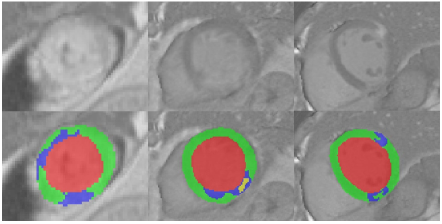

Table 2 shows the quantitative segmentation results of the infection and the no-reflow. The sensitivity of all lesions is significant worse than the corresponding specificity, indicating that most segmentation results are right but many lesions are missed by the proposed method. Figure 3 presents the visualized segmentation results. We can find that most of the missed infraction and no-reflow areas have low contrast and weak boundaries, which are very challenging to segment.

Refer to caption

Figure 3: Visualized segmentation results of the myocardium (green), infraction (blue) and no-reflow areas (yellow).